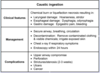

What is the likely diagnosis in a patient that presents with heavy drooling, dysphagia, and a white tongue after being found next to an empty bottle of an unknown substance?

Caustic ingestion

in severe cases, perforation of the esophagus or stomach can occur, resulting in mediastinitis or peritonitis